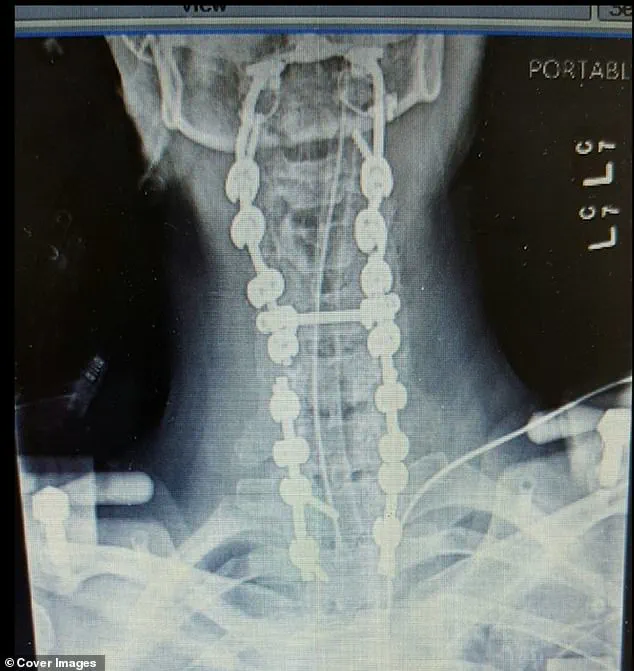

She has now endured a total of 37 surgeries and is fused from her skull down to her pelvis—a procedure that essentially locks her vertebrae in place so they cannot move independently.

The spinal fusion King underwent involves joining two or more vertebrae together, which prevents movement between them but also leaves her unable to shift her head up, down, left, or right.